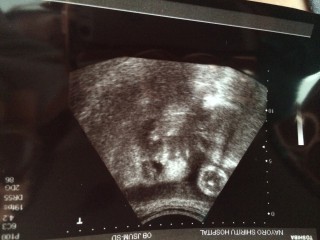

写真:37w0d:ぴよちさん:2,590g

2人目の出産で2,590gとの事です。上の子は2,880gで出産。2人目も同じくらいで生まれるかもねーと言われました!女の子でぷくぷくしてきました!いつ会えるのかドキドキ…楽しみです!